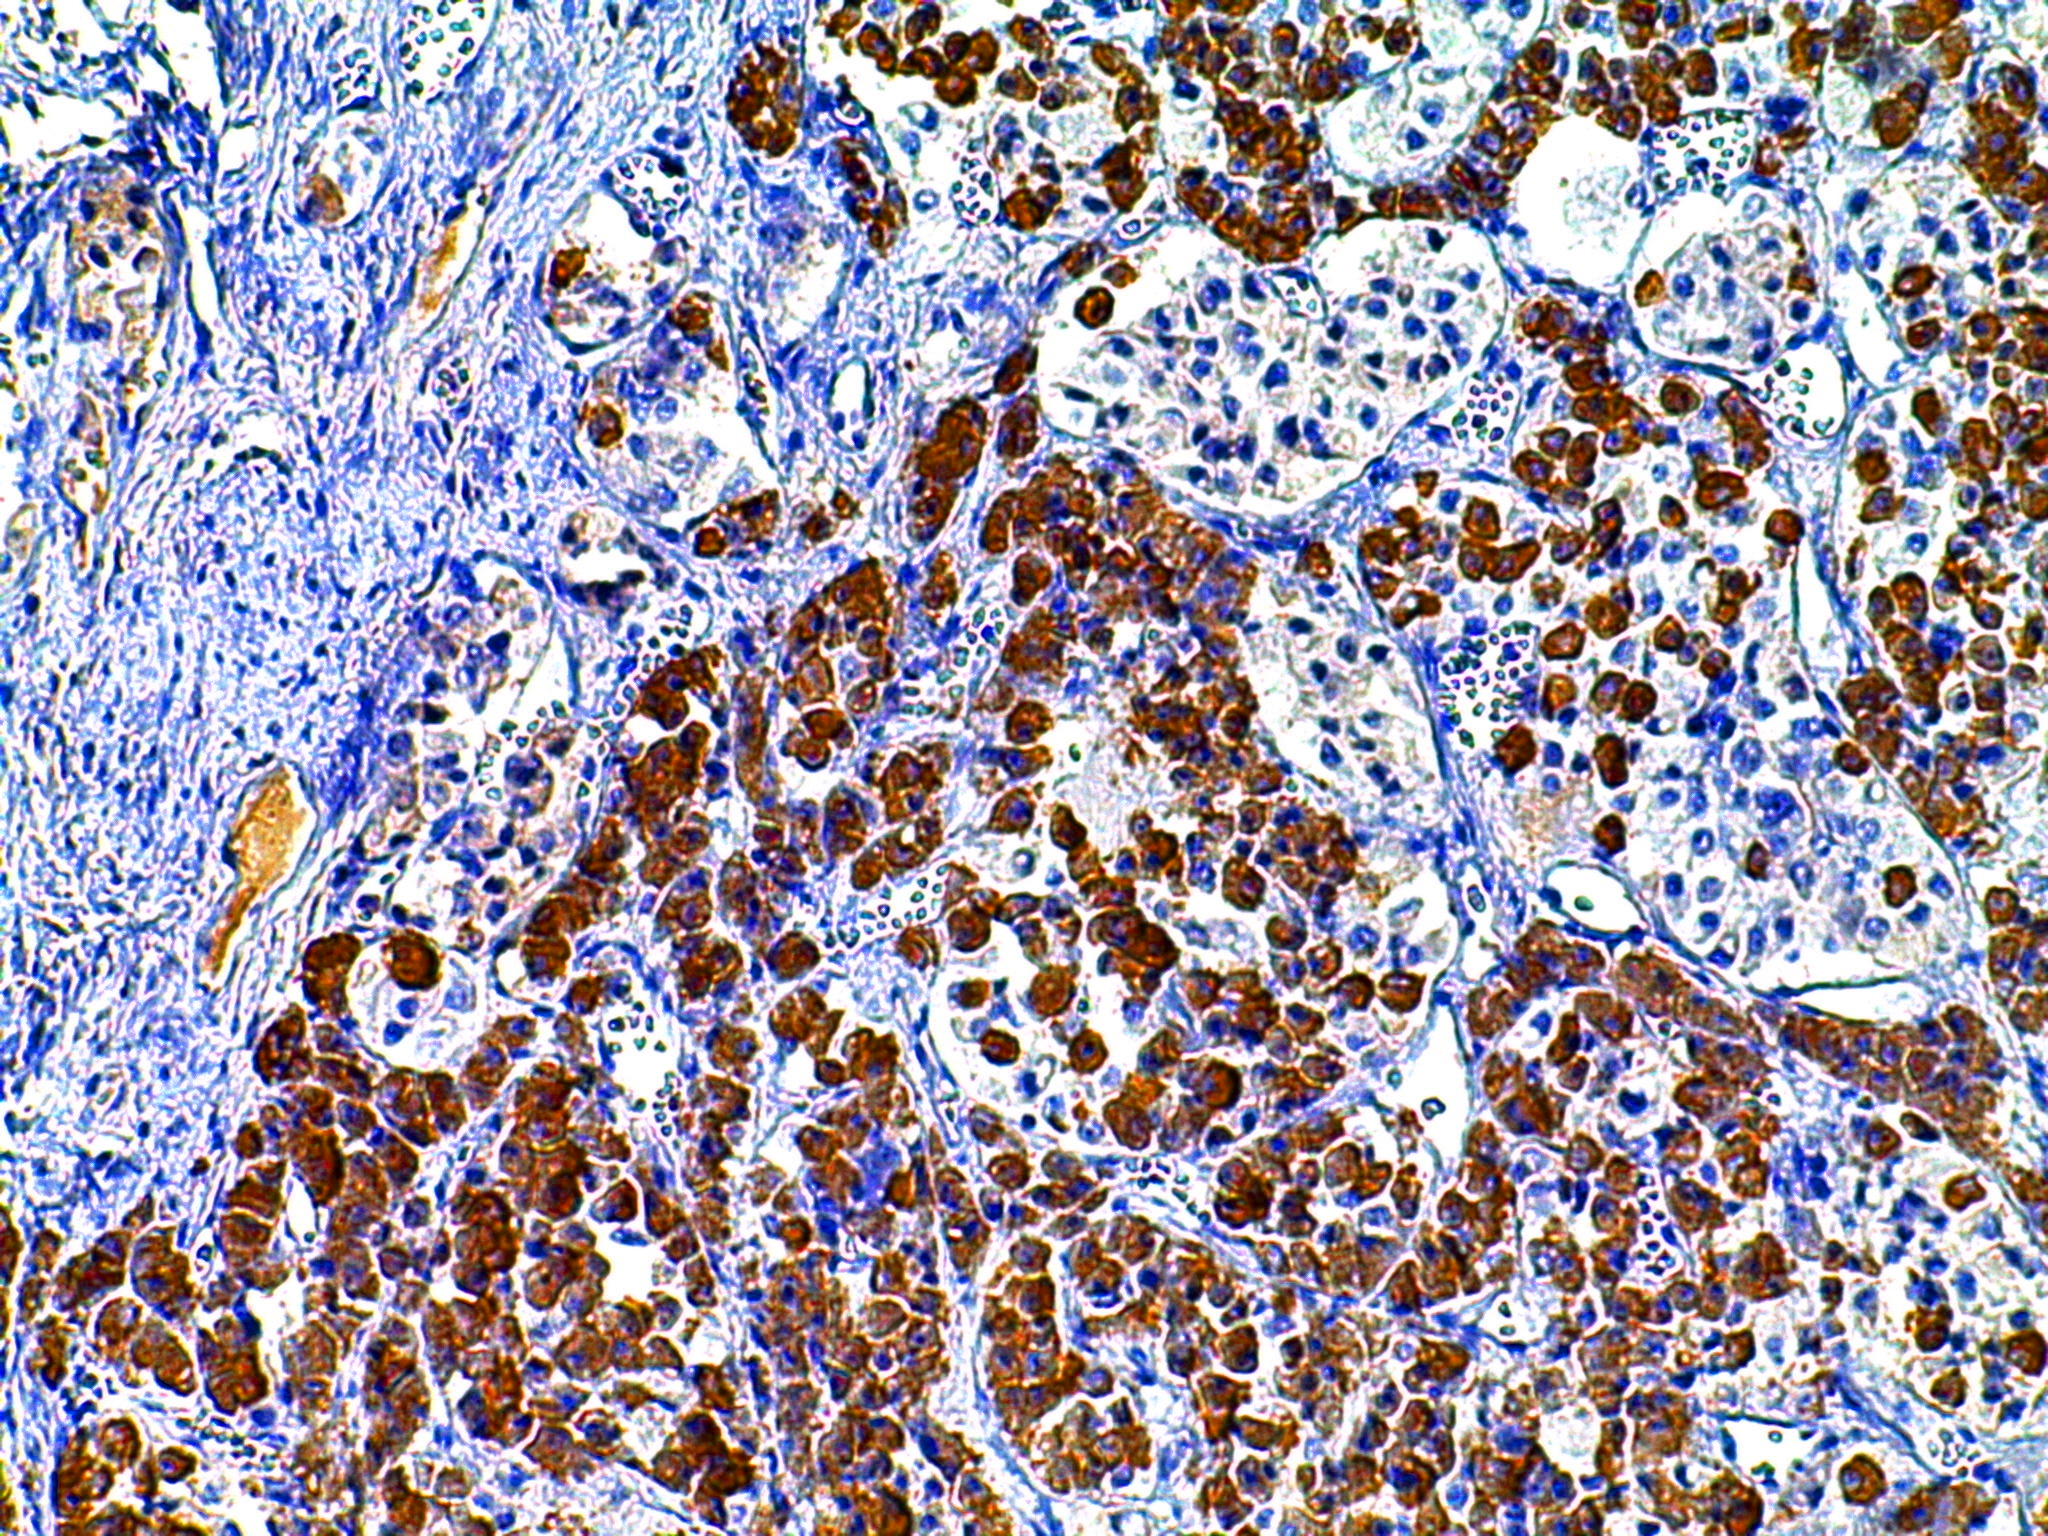

gh 垂体 胞浆